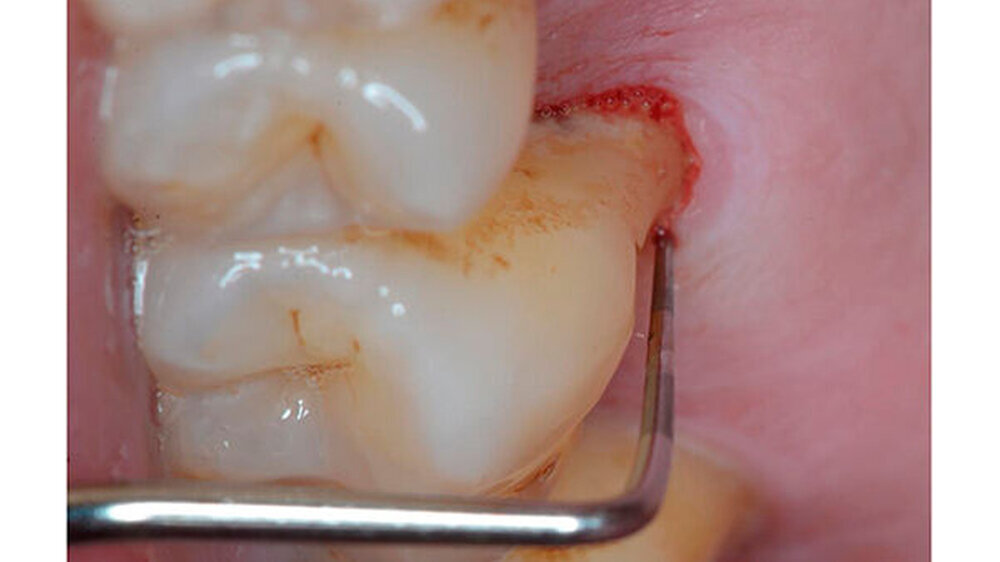

Ein 51-jähriger sportlich muskulöser Patient mit kariesfreiem Gebiss stellte sich zur konsiliarischen Untersuchung vor einer Operation der Kieferhöhle vor. Auf dem OPT imponieren der im Oberkiefer deutlich erkennbare horizontale Höhenverlust mit starker vertikaler Komponente in Regio 15/16 sowie der im Unterkiefer starke vertikale Knochenverlust in Regio 36. Allgemeinerkrankungen oder Medikationen wurden anamnestisch verneint.

Die CT-Aufnahmen zeigen eine deutliche bis zum Orbitaboden heranreichende Totalverschattung der rechten Kieferhöhle. In Höhe des Zahns 16 zeigen sich periradikuläre Rarefikationen als Hinweis auf eine aggressive lokale Parodontitis.